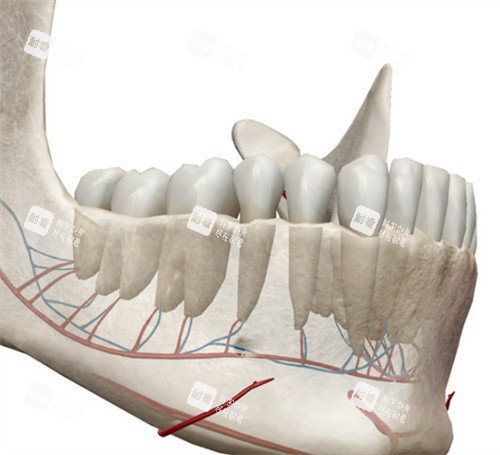

“正颌手术不是切块骨头那么简单,它像在面部搞‘精细拆迁’。”艾伟健医生在诊室里用镊子夹起一块颌骨模型,“上颌要前移3毫米,下颌得旋转5度,咬合关系要像齿轮一样严丝合缝。”他身后的墙上挂着《我国口腔颌面外科杂志》编委的聘书,这是国内颌面领域的头部学术背书。

精度革命:传统手术靠医生经验判断截骨量,误差可能达2毫米;3D导板把误差压缩到0.1毫米,相当于在头发丝上刻字

创伤控制:内窥镜技术让口腔内剥离更精细,术中出血量比传统手术少60%,术后肿胀期缩短40%